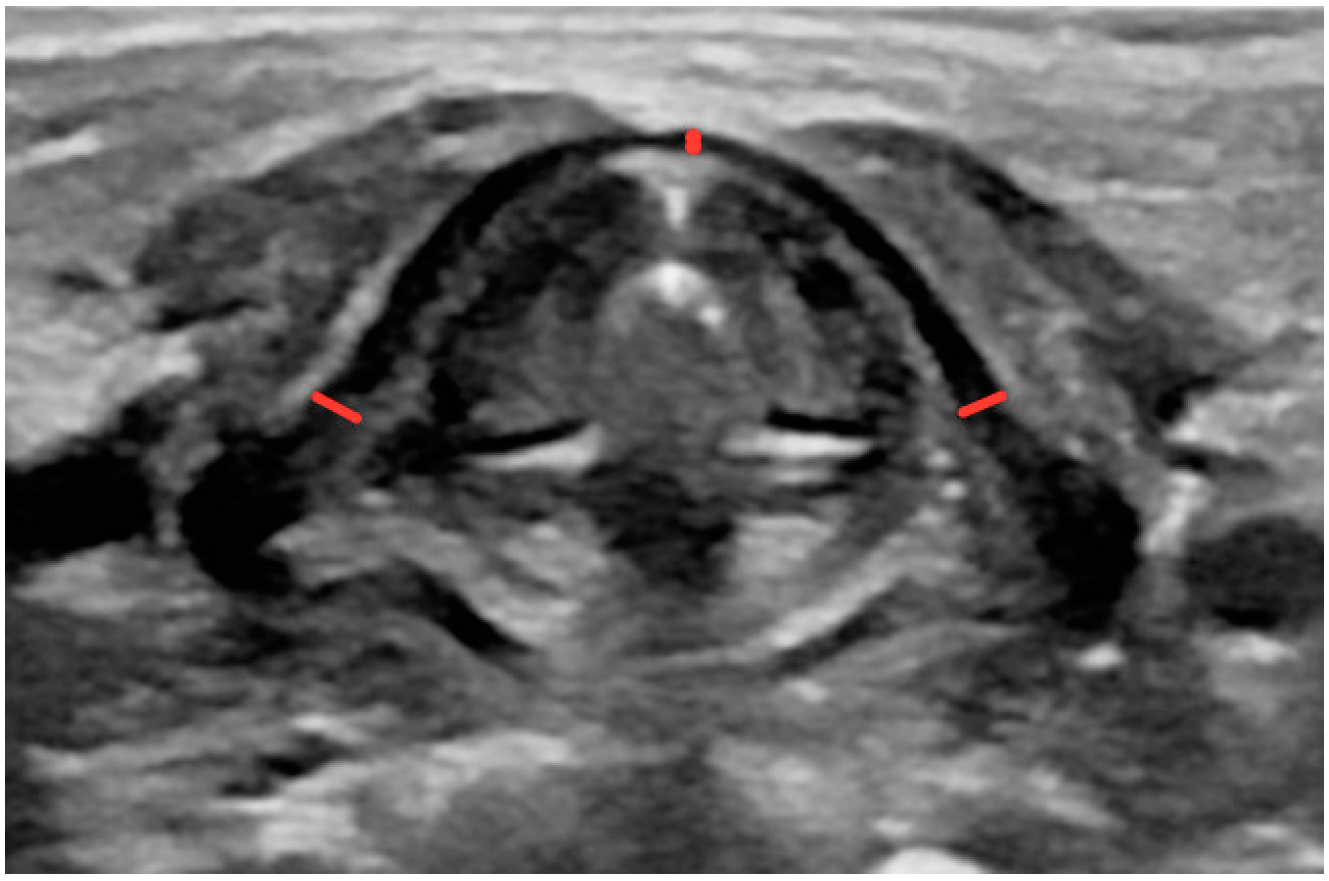

- Angle formed by the lamina of the thyroid cartilage (measurement taken in the transverse plane with two lines drawn tangentially to the thyroid laminae) (Figure A4);